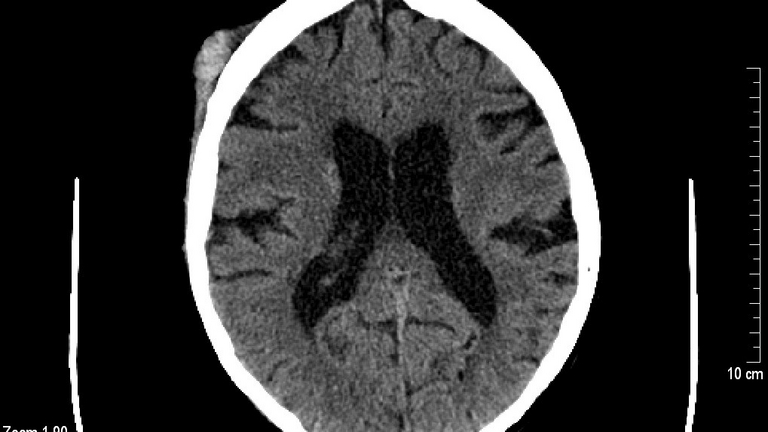

Die Diagnose erfolgt in erster Linie durch eine gründliche klinische Untersuchung. Die Ärztin bzw. der Arzt prüft Bewusstsein, Reflexe, Gedächtnis und Koordination.

- Bildgebende Verfahren wie CT oder MRT werden eingesetzt, wenn Verdacht auf schwerere Verletzungen (z. B. Schädel-Hirn-Trauma, Blutung) besteht.